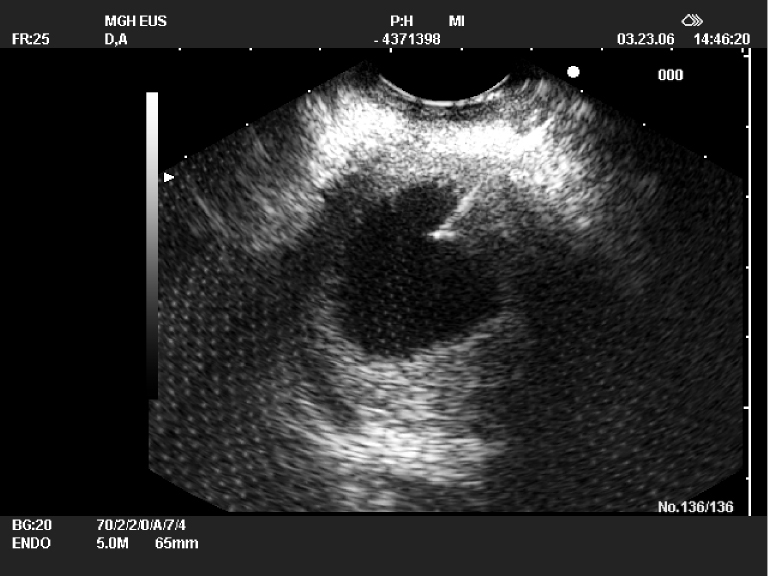

Concern for cystic involvement of the main pancreatic duct rather than the side branches Patients with pancreatic cysts > 1 cm and of indeterminate etiology should undergo additional diagnostic testing in order to determine if the cyst is of high enough risk to warrant either routine surveillance or resection Evaluation with endoscopic ultrasound (EUS) and dedicated MRI sequences can help the clinician to determine if the lesion is mucinous and to evaluate for Pancreatic cysts are small fluid collections that form in the tissue of the pancreas There are many types of pancreatic cysts, from benign cysts to those that can cause cancer These pools of fluid are either filled with a form of mucus and are surrounded by special cells responsible for secreting the fluid into the cyst, or they can simply be collections of pancreatic

Endosonography In The Diagnosis And Management Of Pancreatic Cysts